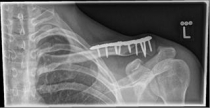

Picture 1 Picture 2

Picture 1: Displaced fracture of the left collarbone before surgery.

Picture 2: After the operation, the fracture is correctly repositioned and held in position with a titanium plate and two screws..